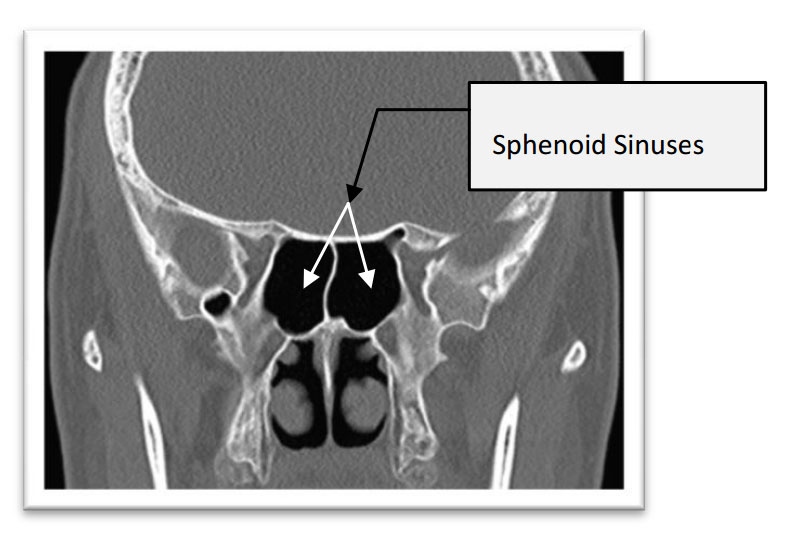

There are four pairs of sinuses. The maxillary sinuses sit within the cheekbones, one on each side, and are the largest. They drain through openings on their upper inner wall, which is anatomically inconvenient because gravity works against drainage and any swelling of the nasal lining can easily block the opening. The ethmoid sinuses are a collection of small air cells sitting between the eye sockets, and they connect the nasal passages to the other sinuses in important ways. The frontal sinuses sit within the bone of the forehead above the eyes and drain downward through a narrow channel. The sphenoid sinus sits deep at the back of the nasal cavity, at roughly the centre of the skull, and when it becomes inflamed and pressurised it produces a distinctive pain at the top of the head or deep behind the eyes that patients often find difficult to place [Fokkens WJ et al. Rhinology. 2020].